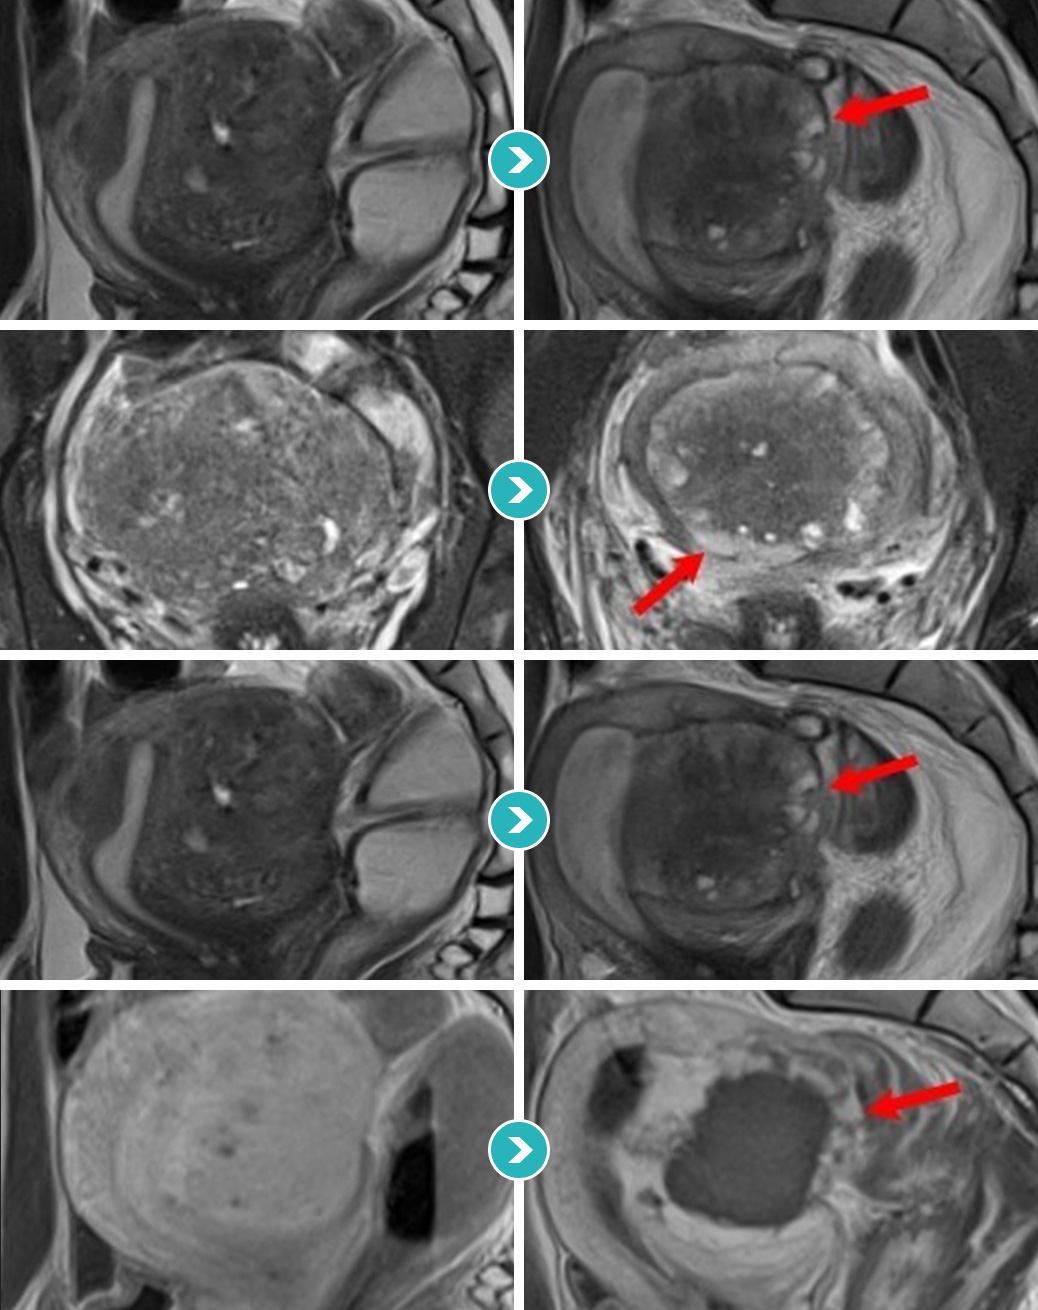

자궁선근증을 4가지 형태(경화형, 결절형, 낭종형, 분산형)로 분류할 수 있으며 각 유형의 맞춤 차별적 시술을 진행합니다.자궁선근증은 환자에 따라 다양한 크기와 유형을 보이기 때문에 하이푸 시술 전에 정확한 치료플랜과 주변 조직에 영향을 주지 않는 정밀한 시술법이 요구됩니다.

심한 생리통과 항문통증으로 자궁선근증이 진단되어 자궁선근증 하이푸 치료를 위해 입원하셨습니다.

하이푸 시술전 MRI사진상 자궁은 6.5크기로 커져서 자궁후벽을 중심으로 자궁선근증성 변화가 관찰됩니다.

아래의 MRI 사진은 자궁선근증 하이푸 시술 전후의 사진을 비교한 사진입니다. 자궁선근증 하이푸 치료후 90%이상 치료되어 치료부위가 회색과 검은색으로

나타나며, 차후에 좋은 경과를 기대하며 가장자리의 잔여병변은 호르몬 치료하면서 경과관찰 하시도록 하였습니다.